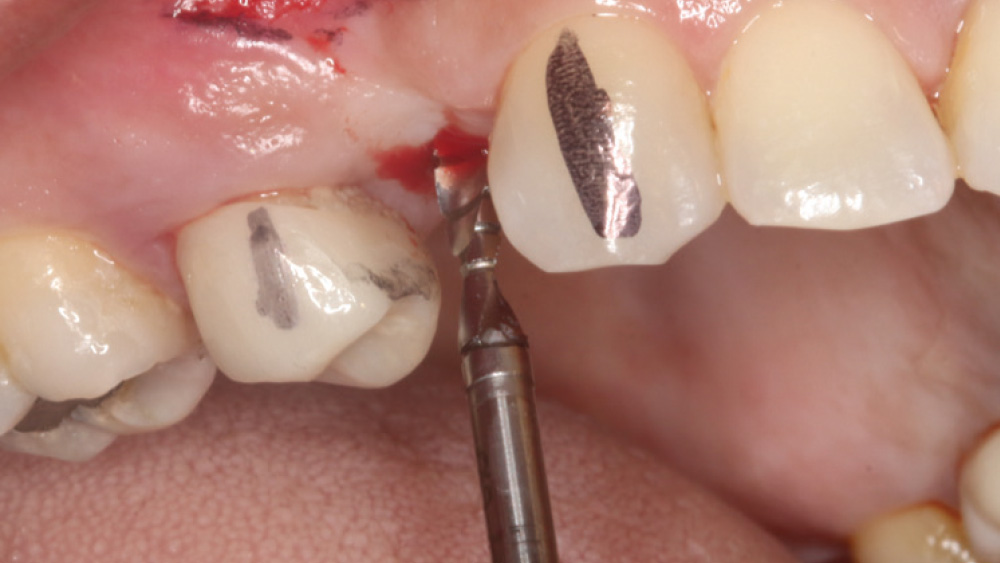

After gaining a clear understanding of the available hard and soft tissue through intraoral evaluation, radiography and — when possible — CBCT scanning, the clinician can determine whether flap reflection or a flapless surgical procedure is ideal for the individual patient. Both of these surgical techniques offer advantages, and the approach should be determined based on the amount of attached tissue present at the implant site, as well as the volume of bone.

When the attached tissue is minimal, a flap procedure allows the surgeon to reposition the flap to create more attached gingiva and improve the interdental papillae at the implant site. Reflecting a gingival flap also enables the practitioner to more clearly see the final position of the implant at the crest of the bone. If it’s necessary to visualize the bone during the surgical procedure due to uncertain ridge width or height, flap reflection is the safest, most predictable approach.

The following case, which I performed alongside Dr. Stephanie Tilley of Pensacola, Florida, illustrates the use of both surgical techniques for the same patient, who presented with edentulous spaces in the areas of both right and left maxillary first bicuspids. Due to varying soft-tissue volume on each side of the arch, implant surgery was performed using a flapless procedure for one site, while the attached gingiva was reflected to expose the available hard tissue for the other. As a result of proper site evaluation, treatment planning and restorative-driven implant placement, both surgical techniques led to successful outcomes for the patient.